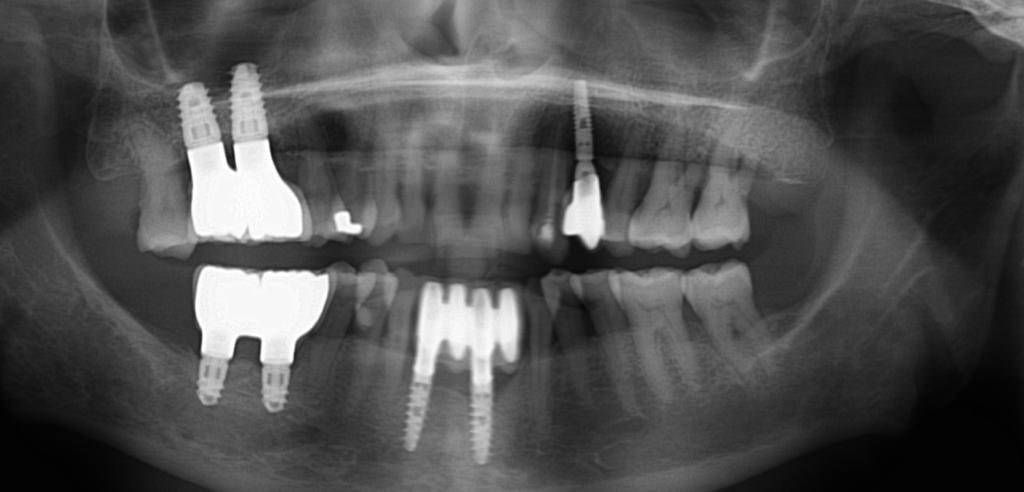

Buenos dias , ¿Alguna idea de la marca de implantes superiores o conexion compatible? Muchisimas gracias de antemano, Un saludo, Rocio

Buenas tardes compañeros. Nos envían este caso de los compañeros de LUSOBIONIC ESPAÑA a ver si les podemos echar un cable y averiguar qué implantes son. Gracias!

Paciente viene a la consulta para cambio de coronas y no sabe que implantes le colocaron. Ayudenme a identificarlos. Gracias.😊